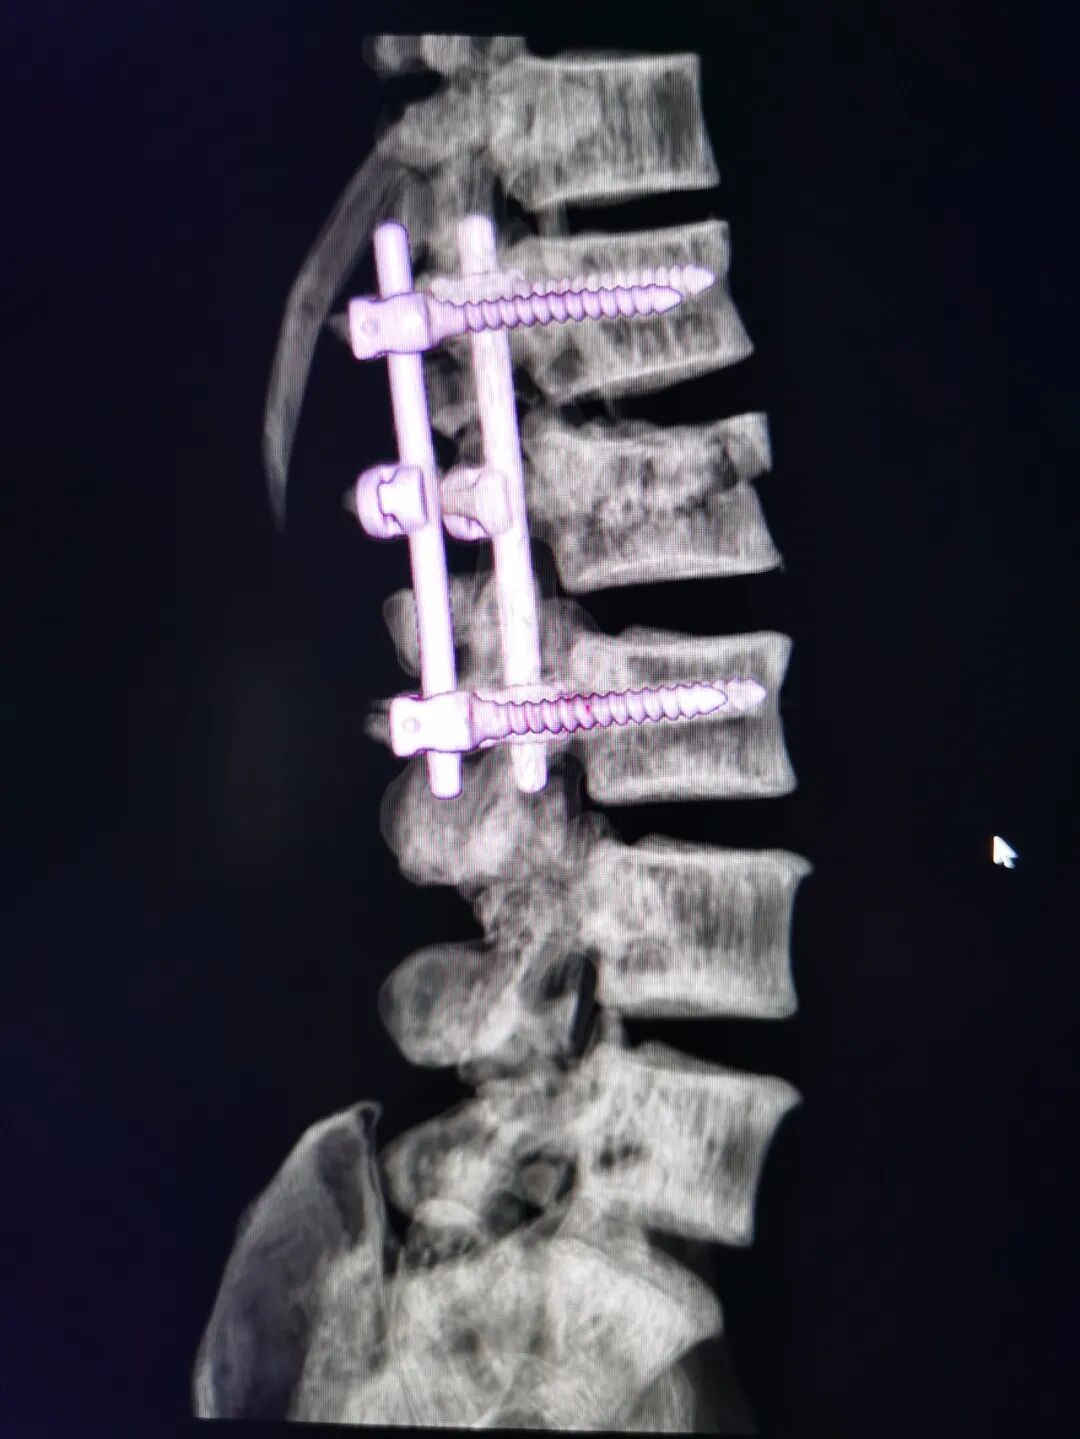

之后,我院骨外科安排对李先生做了进一步详细的检查,对患者病情做了更全面的评估。确诊李先生为2椎体爆裂性骨折,且碎裂的骨折块向后脱位占据了80%椎管面积,马尾神经受压,腰2棘突骨裂。

如果错过最佳治疗时机,则可能造成截瘫。我院骨外科专家团队,由副主任医师彭明、院长刘文松牵头,以及骨外科其他同仁一起,针对李先生的情况进行了会诊,决定立即对患者进行腰2椎板减压脊柱内固定手术。

这是种极少发生的情况,如果医生当时没有敏锐的专业直觉与丰富的行医经验,依旧按照传统方式进行手术,极大可能会加重损伤。最后,经过数小时的努力,终于成功对李先生完成了椎板切除减压椎弓内固定术。

脊柱内固定技术已经有近半个世纪的发展历史,并随着脊柱生物力学研究和材料科学的发展取得了巨大进步。在脊柱退行性疾病、脊柱肿瘤、创伤以至于脊柱感染等手术治疗中得到了广泛应用。内固定的意思就是手术打开了以后,换一种金属的内置物放到体内去矫正骨折产生的畸形、错位,还有对脊柱进行稳定、恢复脊柱的功能,也就是说通过手术内置物的办法叫做脊柱内固定。目前,椎弓根螺钉(材料一般为医用不锈钢、纯钛或者钛合金等)内固定系统能够有效完成脊柱的三柱固定,符合脊柱固定的生物力学要求,是常用的脊柱内固定系统。此手术可有效解决患者痛苦、改善患肢功能,能尽早地使患者恢复锻炼功能。

另外,值得一提的是我们为李先生使用的是钛合金椎弓根螺钉,这种螺钉的优势特别明显,首先与医用不锈钢相比,钛合金与机体有更好的生物相容性,其弹性也更加接近骨组织;其次,由于钛合金制与磁场之间没有相互作用,使病人手术后仍然能够安全的接受核磁共振检查,从而提高脊柱损伤病人的手术治疗水平,是目前最好的内固定物材料之一。